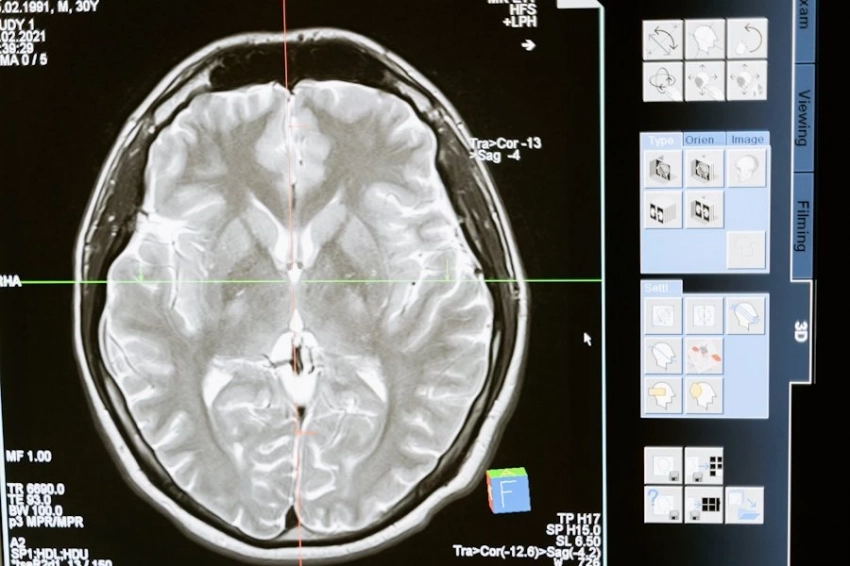

Учеными из Колумбийского университета прослежена связь между болезнями сердца и ухудшением деятельности мозга.

Как сообщает журнал Nature Neuroscience, американские ученые провели эксперимент на мышах, продемонстрировавший, что к сердечной недостаточности может привести неверная регуляция кальция в сердечных клетках. А сбои сердечного ритма, в свою очередь, негативно отражаются на функционале мозга.

На людях-добровольцах также было проведено исследование, показавшее, что у пациентов с сердечной недостаточностью наблюдается наличие негерметичных кальциевых каналов в сердце.